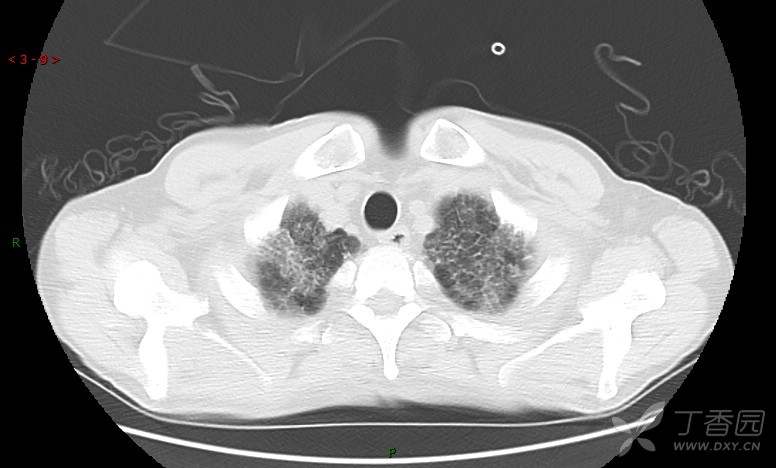

患者男,42岁,咳嗽半年余,加重伴憋喘2月余。

患者半年余前无明显诱因出现间断咳嗽,干咳为主,偶咳少量黄白痰,剧烈咳嗽或运动后可出现轻度憋喘,无高热、脓臭痰,无胸痛、咯血及晕厥,无低热乏力及盗汗,无心前区压榨感及夜间阵发性呼吸困难,初未在意,未予正规诊治。2月余前患者自觉上述症状较前加重,咳嗽、憋喘明显,黄白色粘痰略有增多,伴有发热,热前伴有畏寒、寒战,体温最高达38.9℃,先后就诊多家医院,入住重症监护室,未行气管插管,考虑“重症肺炎”,给予“美罗培南、复方磺胺甲噁唑”等药物抗感染,“卡泊芬净”抗真菌,并给予“甲泼尼龙”等药物治疗35天,经治疗后症状好转于2018-04-02出院。患者自出院后仅应用中药治疗(具体不详),并给予家庭氧疗,平素仍有间断咳嗽,咳少量黄白色粘痰,活动后憋喘明显,活动耐量差,以卧床为主。